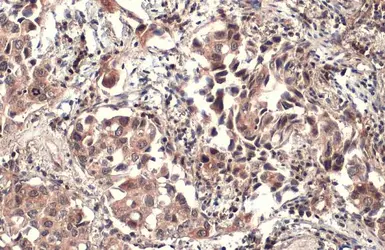

Anti-Pez antibody [C2C3], C-term used in IHC (Paraffin sections) (IHC-P). GTX105769

GTX105769 IHC-P Image

Immunohistochemical analysis of paraffin-embedded human lung papillory adenocarcinoma, using Pez(GTX105769) antibody at 1:500 dilution.

Antigen Retrieval: Trilogy™ (EDTA based, pH 8.0) buffer, 15min